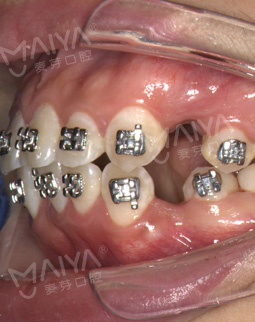

2016/09/01 矫正过程中

逐渐的我都可以吃一些稍微硬一点的东西了。麦芽的服务是真的贴心,还有客服打电话来,不同的是,以往印象中的客服都被当成骚扰电话一样,但是我接到电话的时候,客服小姐姐和温柔,问我感觉怎么样,有问题的话可以直接找他们,心里真的很感动!麦芽真的是一家很温馨的医院,人情味很浓,当然了我是实事求是的说好就好,想矫牙的仙女们接到电话的时候如实反馈就好了,就是别把人家当骚扰电话哈,嘻嘻~~~

2016/08/15 矫正过程中

“复诊医生都会贴心提醒,躺在牙椅上的时候,张主任都会用数字化3D口扫给我重新检测咬合关系,一点点调整,所以矫牙真的是个精细活,如果没有步入矫牙大军,很多细节我到今天可能都不清楚。现在牙齿逐渐排齐,脸型也慢慢在改变,好期待改变后的自己!”